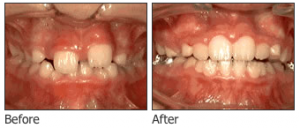

- Metal Braces: A Trusted Solution for a Perfect Smile